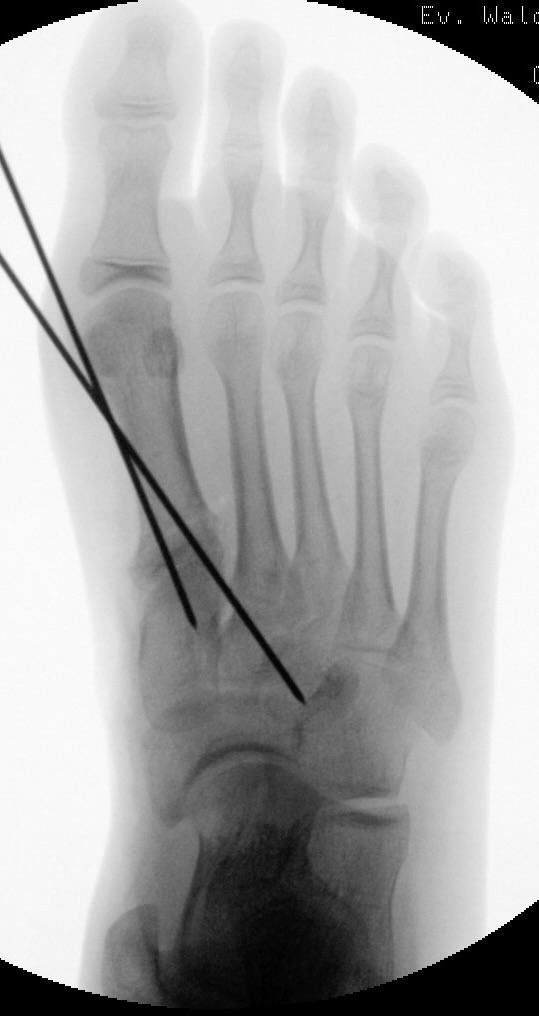

Liegt eine stark subduktische 5. Zehenposition vor, fräsen wir bevorzugt in der Kramertechnik für eine maximale Korrektur und Setzen für zwei bis drei Wochen einen intramedullären Draht nach proximal durch die Osteotomie (Abb. 27).

Abb. 27 a-d: Radiologische Darstellung intraoperativ (a) und vor dem Entfernen des Drahtes einer kompletten Schaftosteotomie mit intramedullärem Draht stabilisiert (b). Die Osteotomie wird minimalinvasiv durchgeführt und der Draht nach der Spülung über den gleichen Hautschnitt einfach in den Schaft hineingeschoben und die Osteotomie darüber stabilisiert. Das Köpfchen kann anschließend je nach Bedarf plantarisiert oder extendiert werden. Radiologische Verlaufskontrolle vor Entfernung des Drahtes (c-d).

Zum Lesen der Bildbeschreibung und zur Vollansicht bitte die Bilder anklicken. Bilder: A. Helmers.

Anschließend kann, falls erforderlich, mit Tape weiter stabilisierend gezügelt werden. Nicht selten verschieben wir um die gesamte Schaftbreite mit guter Heilung des Knochens.